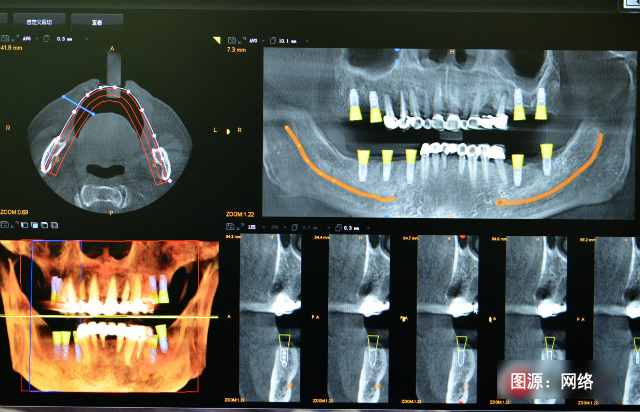

受植區(qū)良好的骨條件是實(shí)現(xiàn)植體與骨整合的重要因素,為了預(yù)防及減少牙槽嵴的廢用性萎縮和吸收,使牙槽嵴骨量的高度、寬度及密度滿足后期種植的需要,需在拔牙后種植前對(duì)其位點(diǎn)進(jìn)行保存,即拔牙后軟硬組織量的保存。

3、即刻種植:拔牙后即刻植入種植體是預(yù)防牙槽嵴萎縮的一個(gè)有效方法,它能夠很好地保持牙槽嵴的高度和寬度。